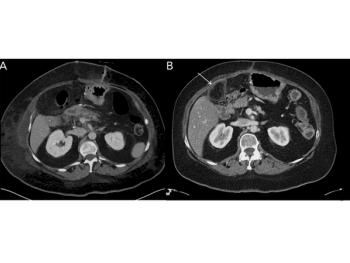

CT images from a 58-year-old female who underwent surgery for pancreatic cancer show a previously unseen structure. What is your diagnosis?